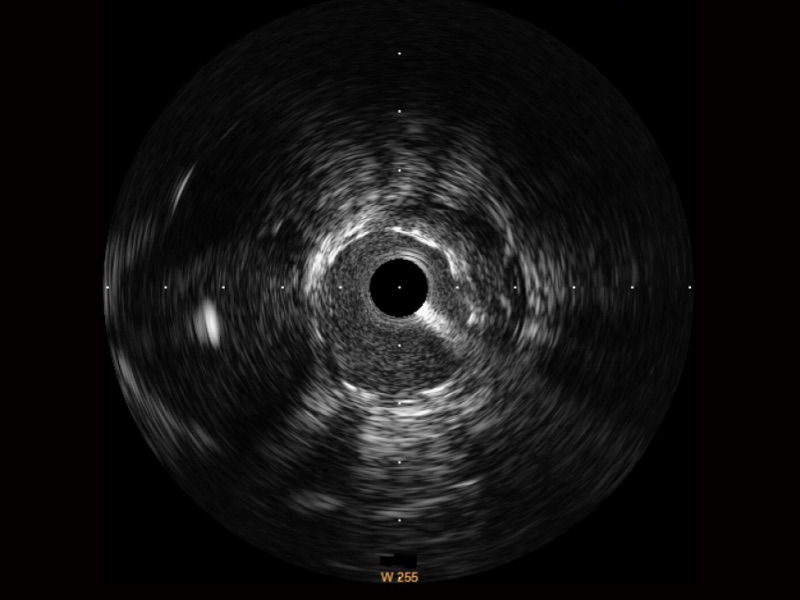

传统IVUS图像

对比传统IVUS导管成像,16877太阳集团宽频IVUS图像的近场支架梁显影更细腻,远场中膜外血管仍清晰可辨,兼顾远中近,兼顾分辨力与穿透深度